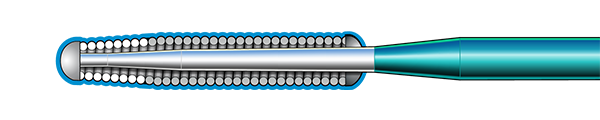

Inner Coil Technology

The advanced design of the stainless steel core and Inner Coil Technology provides a unique combination of exceptional torqueability, rail support, and shape retention.

- Stainless steel inner coil affixed directly to the distal end of the guidewire core

- Improved durability and ease of shaping

- Exceptional torqueability without whipping